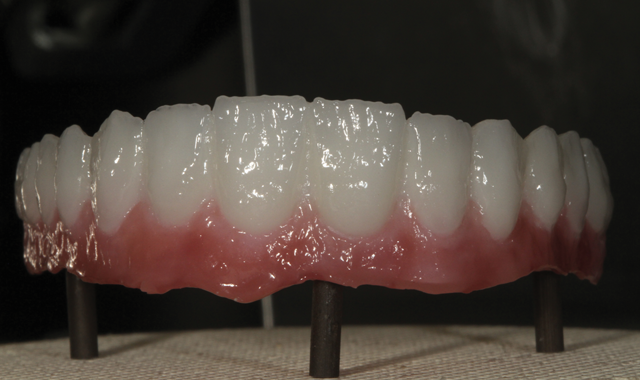

Fig. 10 Finished restorations

The final restoration was then seated on the model after the titanium base was cemented to the zirconia framework (Fig. 10), not before shown. In a mirrored image, the final restoration is shown for the reader in order to note the tissue area indentation and color, whitish-pink with texture.